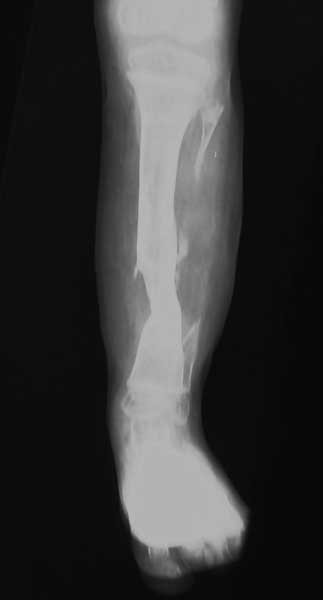

Хочу поделиться с вами опытом недавно пролеченного мною мальчика пяти лет с врожденным псевдартрозом. ‚ вначале ему была пересажена малоберцовая кость. Операцию проводили с пластическими хирургами. Шесть месяцев спустя малоберцовка приросла, и мальчик начал ходить в специальном бандаже. —через некоторое время вследствие неаккуратности родителей (кто-то сел на ногу ребенка) произошел перелом на уровне стыка. Попытка срастить, наложив аппарат, была неудачной. Поэтому было принято решение удалить пересаженную малоберцовую кость и заместить дефект за счет верхней кортикотомии. Срок лечения один год. Был достигнут положительный результат. Спустя полтора года повторного перелома не наблюдалось.